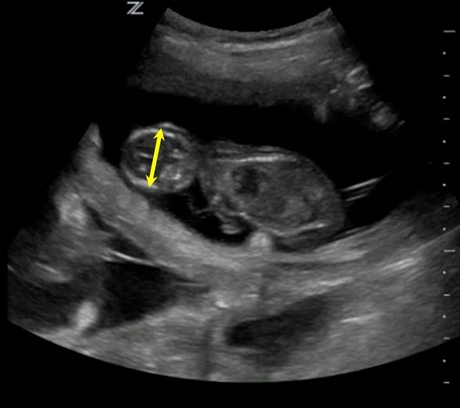

A confirmação da gestação pode ser realizada por volta de 17 dias após o pico de LH. Entre 20 e 25 dias, a única medida disponível para cálculo da idade gestacional é o diâmetro da vesícula embrionária. O embrião passa a ser visível a partir de 26 dias e a partir de então, o comprimento cabeça-nádega e o diâmetro do corpo podem ser mensurados. O diâmetro da cabeça (biparietal) pode ser medido com mais precisão a partir de 30 dias. Os estudos mostram que a precisão da predição de data de parto (65 dias ± 2 dias) é de 87%. A predição tem mais erro em raças pequenas ou gigantes e para isso se usa um fator de correção de mais um dia para as raças pequenas (<9kg) e menos dois dias para as gigantes (>40 kg). Os cálculos não são muito confiáveis no final da gestação, pois ocorre maior variação de crescimento fetal nesse momento. A observação do desenvolvimento dos órgãos do feto também pode ser utilizada para estimar a idade do feto.

Diâmetro biparietal